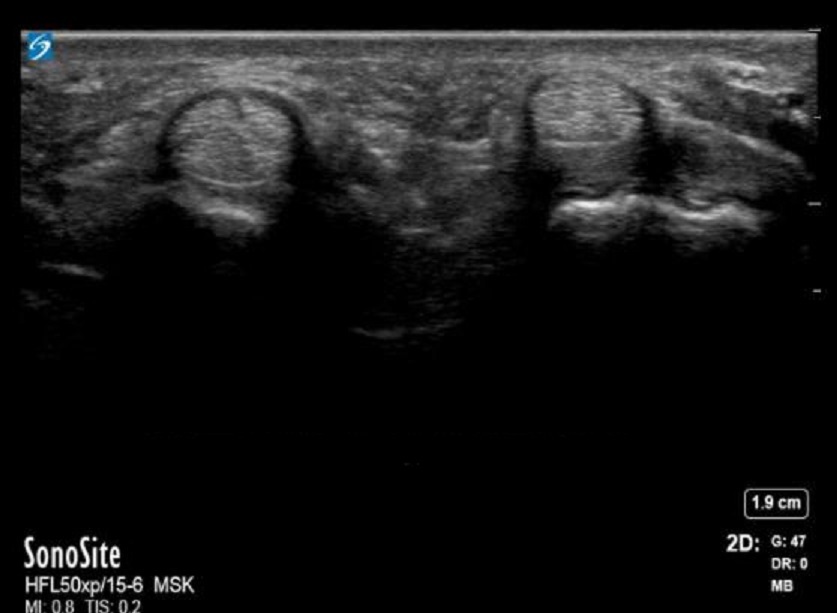

手部 A1 滑车横切面(未标记)

Palmer 手部 - A1 滑车横切面